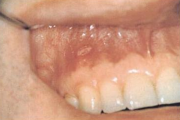

Aftoosne stomatiit

villikesest tekkinud haavand suu limaskestal